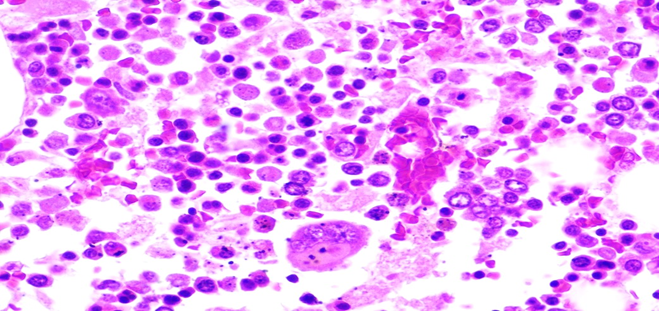

Figure 5A: Photomicrographs showing hemophagocytosis by macrophages in lymph node (H&E, 60X magnification).

Figure 5B: Photomicrographs showing hemophagocytosis by macrophages in bone marrow (H&E, 40X magnification).

Figure 5C: Photomicrographs showing hemophagocytosis by macrophages in spleen (H&E, 40X magnification).